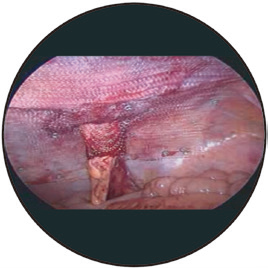

? ? ? ? Dyna Mesh-IPST造口旁疝專用補片

■獨一無二的3D袖口設計,依靠編織技術,無縫連接,是化平面為立體的卓越產(chǎn)品,保證術后復發(fā)率最低。